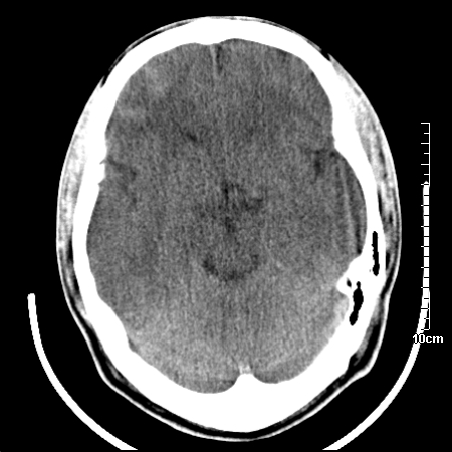

4天上述症状加重伴左侧肢体发软,复查ct,

右側额叶、放射冠区灰白质改变,建议ct增强或mri检查

右侧基底节区低密度灶,建议磁共振检查。

右侧放射冠区混杂密度灶,边缘不清,病人较年轻,结合有发热病史,支持感染性病变,建议密切结合临床可抗感染治疗后复查。

右侧颞叶病变定性困难,既然发病急,又有发热,脑脓肿不能除外。

右侧颞叶混杂密度灶,强烈建议:增强ct检查